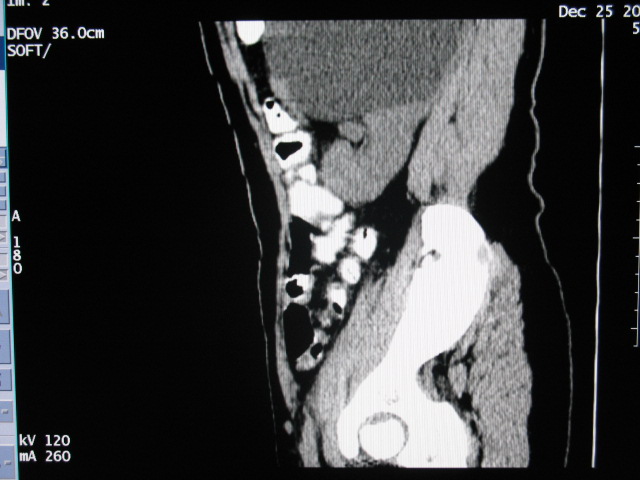

女,28岁,自觉腹部包块一年余

左侧重复肾、双输尿管畸形。重复肾一般上位肾发育不良,易合并积水。

考虑左侧双肾盂双输尿管畸形,其中一输尿管末端梗阻(不排除异位开口可能,不知病人有无不自觉溢尿,有可能开口于阴道或宫颈,也可下端为盲端)并相应之肾盂及输尿管明显扩张积水。

术后证实是左侧双肾盂双输尿管畸形,巨输尿管巨肾盂症